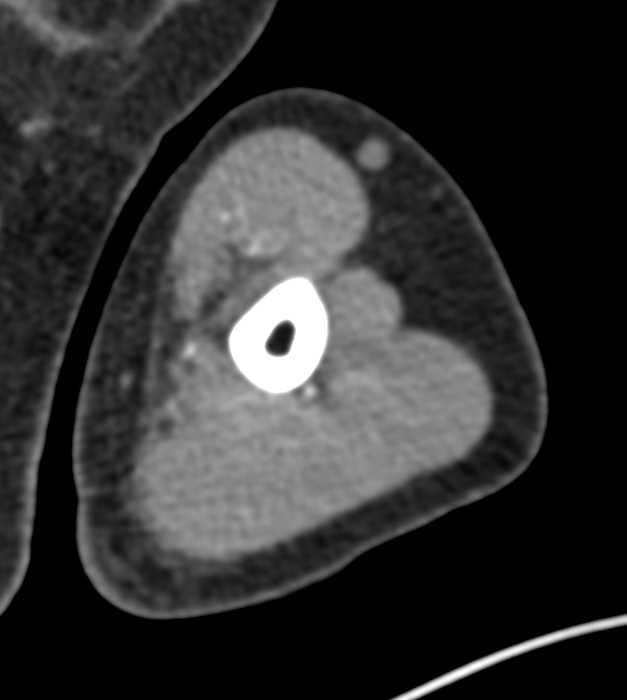

Brachial Artery Occlusion